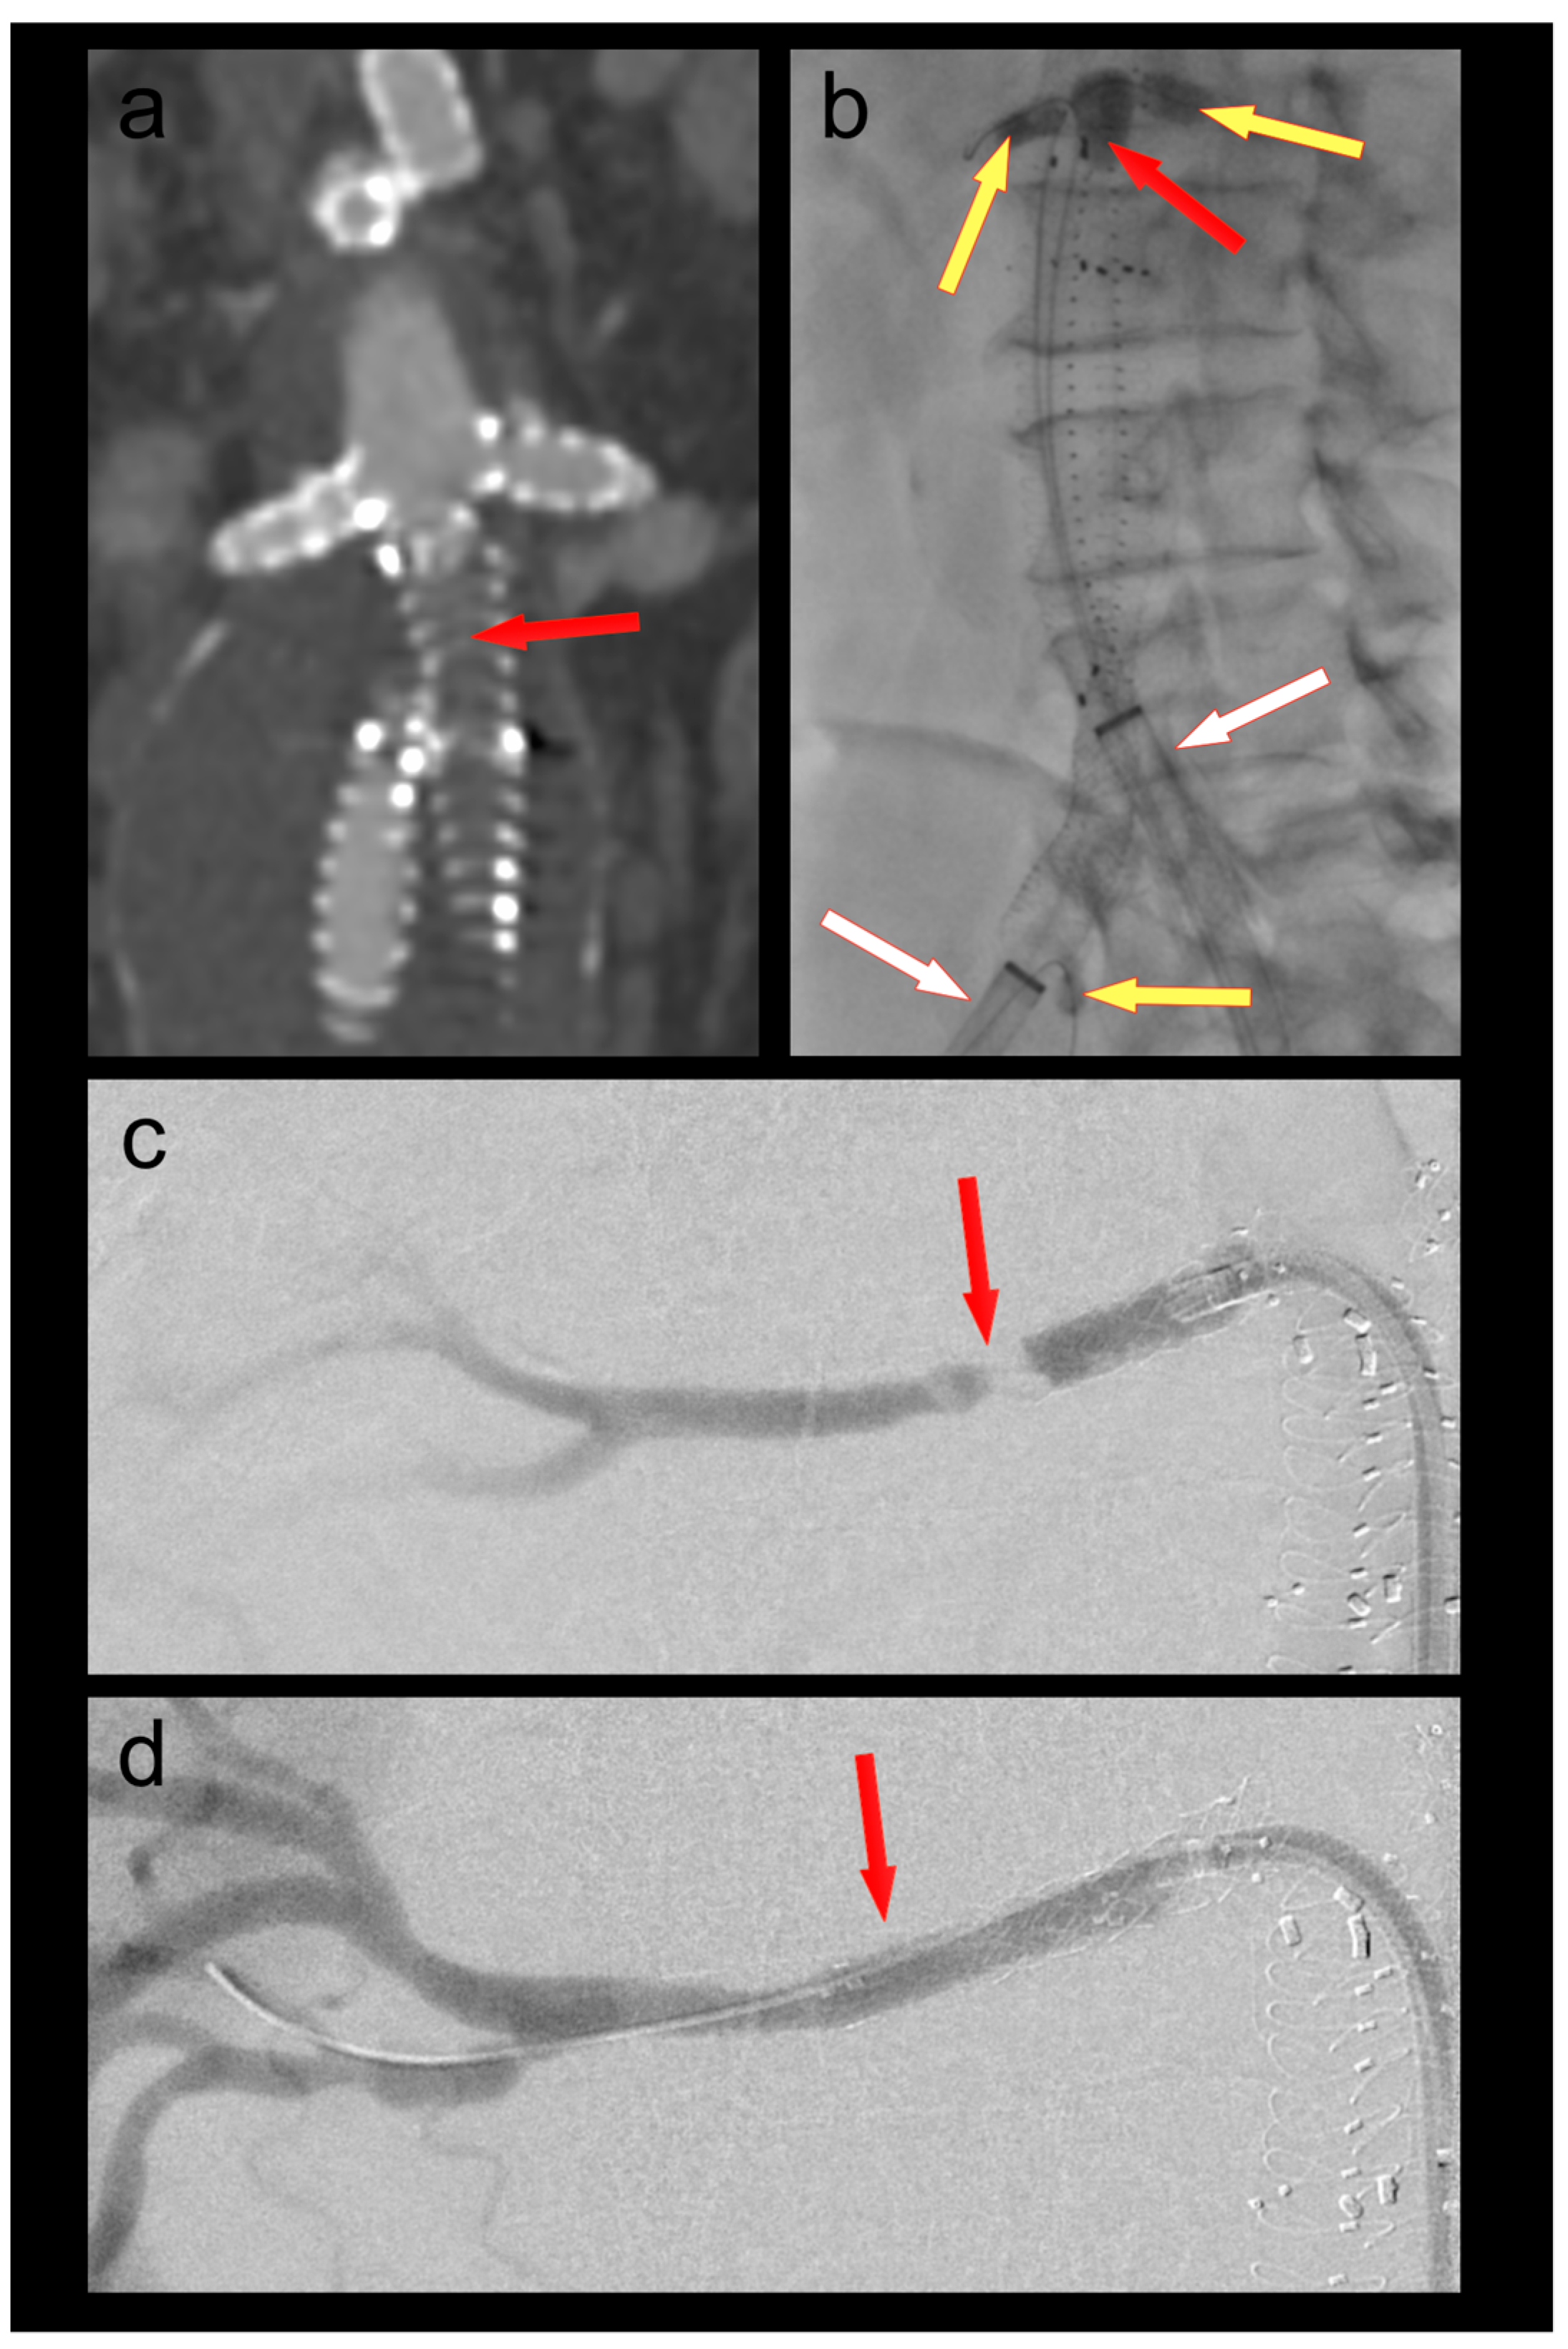

3.2. Patient 2

A 61-year-old female patient was admitted because of respiratory failure due to bilateral COVID-19 pneumonia. A CT angiography detected several appositional thrombi throughout the thoracoabdominal aorta, the biggest of which was located at the origin of the coeliac trunk (Figure 2). Another scan two days later showed progression of the thrombi in spite of therapeutic heparin. The coeliac trunk was nearly occluded, and the right hepatic artery was completely occluded. Furthermore, the patient had acute cholecystitis. To avoid further embolization, we decided to thrombectomize the aorta and the origin of the coeliac trunk. The coeliac trunk, superior mesenteric artery, and both renal arteries were protected by OTW Fogarty® catheters, while the hypogastric arteries were protected by advancing the large-bore sheaths into the common iliac arteries. Thrombectomy of the entire aorta into the large sheaths was performed using an 8–22F Fogarty® occlusion catheter (Figure 2). The 5.5F Fogarty catheter that blocked the coeliac trunk was then used to thrombectomize its origin. There was no relevant residual thrombus in the aorta or the coeliac trunk on completion angiography (Figure 2). No further thrombotic complications were seen under therapeutic anticoagulation, and the patient was discharged home after several months in the hospital.

Figure 2. (a) Thrombus in the aorta and in the origin of the coeliac trunk (red arrow); (b) thrombectomy (red arrow) of the thoracoabdominal aorta under balloon protection of the coeliac trunk, superior mesenteric artery, and both renal arteries (yellow arrows). The large-bore sheaths are occlusive in both common iliac arteries (white arrows); (c) Postoperative CT scan with no residual thrombus in the aorta or the coeliac trunk (red arrow).